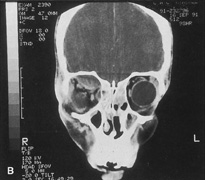

Fig. 16. A. Patient with right orbital cellulitis. B. Coronal CT scan demonstrating subperiosteal abscess formation from frontal and ethmoidal sinusitis. C. Frontoethmoidal orbitotomy incision marked for abscess drainage.

The periosteum is exposed and incised with a Freer elevator and then is reflected off the bone posteriorly. It is generally quite adherent to the curved contour of the medial canthal bones, especially at the medial canthal tendon. The anterior lacrimal crest is encountered inferiorly. Care should be taken not to damage the lacrimal sac with the elevator. The posterior lacrimal crest is visible behind the sac. Adequate mobilization of the periosteal connections to the anterior lacrimal crest gives a large area of exposure. The periosteal elevation is carried superiorly in the area of the trochlea. Elevation of the periosteum opens the subperiosteal space. Blood or pus caused by fracture or infection, if present in this space, is encountered at this point.

Elevation of the periorbita along the medial orbital wall posterior to the lacrimal sac progresses easily. Orbital fractures involving the thin ethmoid bone are seen at this point. The anterior ethmoidal artery is seen at the junction of the ethmoidal and frontal bones where the orbital roof meets the medial orbital wall (see Fig. 7). Usually it is found on a line extending posteriorly from the superior border of the medial canthal tendon. This artery either should be thoroughly cauterized with the bipolar cautery or clipped with a vascular clip before cutting. As the dissection in the subperiosteal space moves posteriorly, the orbit narrows. The posterior ethmoidal artery is identified. This is a reliable landmark for the optic foramen, which lies approximately 5 mm behind the ethmoidal artery.

Indications

The frontoethmoidal medial orbitotomy allows access for a variety of procedures in the subperiosteal and peripheral surgical spaces and sinuses (Fig. 17). Its main use is for processes involving both the frontal or ethmoid sinuses and the orbit. Entrance into the subperiosteal space is obtained easily. Drainage of subperiosteal blood or pus occurs as the space is entered.

Fig. 17. Schematic demonstration of areas amenable to frontoethmoidal orbitotomy. Coronal (A) and axial (B) views. This approach can be used for exposure of the medial orbit, ethmoid and sphenoid sinuses, and optic canal.